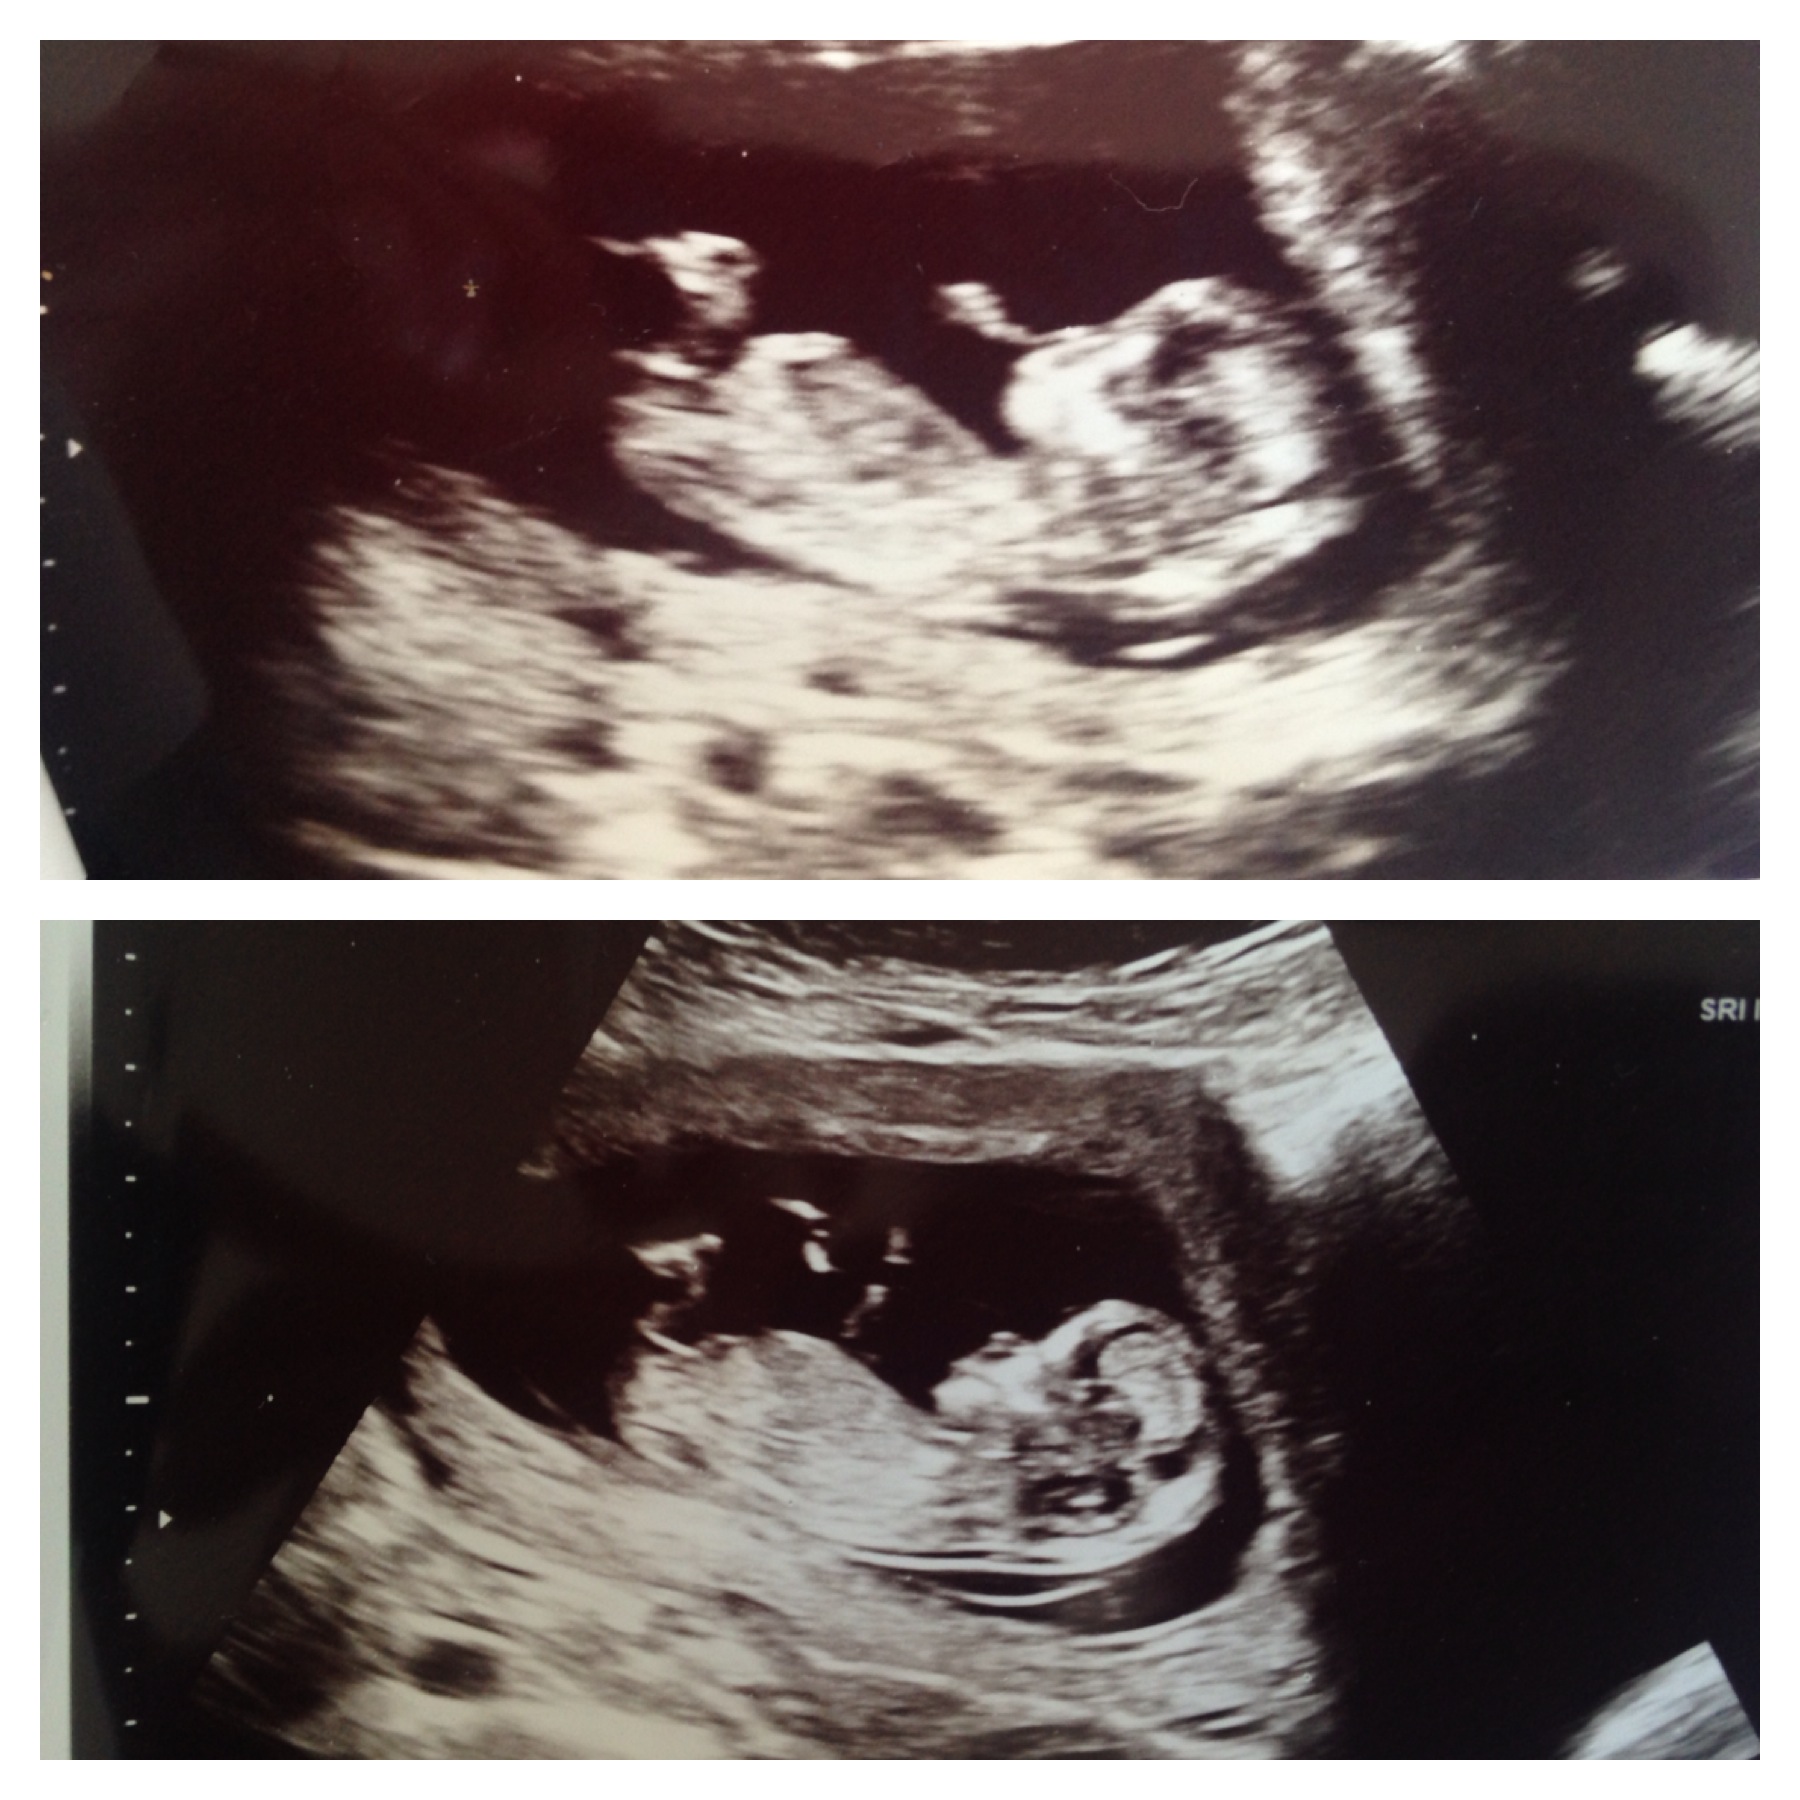

Shots from yesterday at 12w 1d. Any guesses?? Please and thank you!

Difficult one. The first nub looks pretty flat but the second one seems to be on the rise. So I'm going to say 60/40 for boy.

Here is one more shot in case it helps :) Thank you!

Boy, based on the shape of the skull

Boy from second pic

boy lean looks like their might be a stack but not confident.